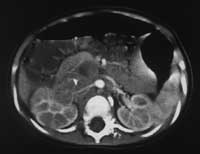

Рис. 5. Нефробластома справа у больной П., 6 лет.

А-Б, С-Д – опухолевый тромб (дефект контрастирования) в просвете НПВ, контрастное вещество визуализируется в просвете сосуда тонкой пристеночной полоской (А).